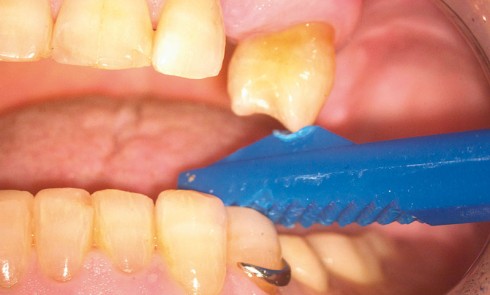

Article réservé à nos abonnés Diagnostic des fractures longitudinales dentaires

Les fractures dentaires longitudinales sont classées en cinq catégories [3] (fig. 1) : – les craquelures de l’émail : il s’agit de fêlures...